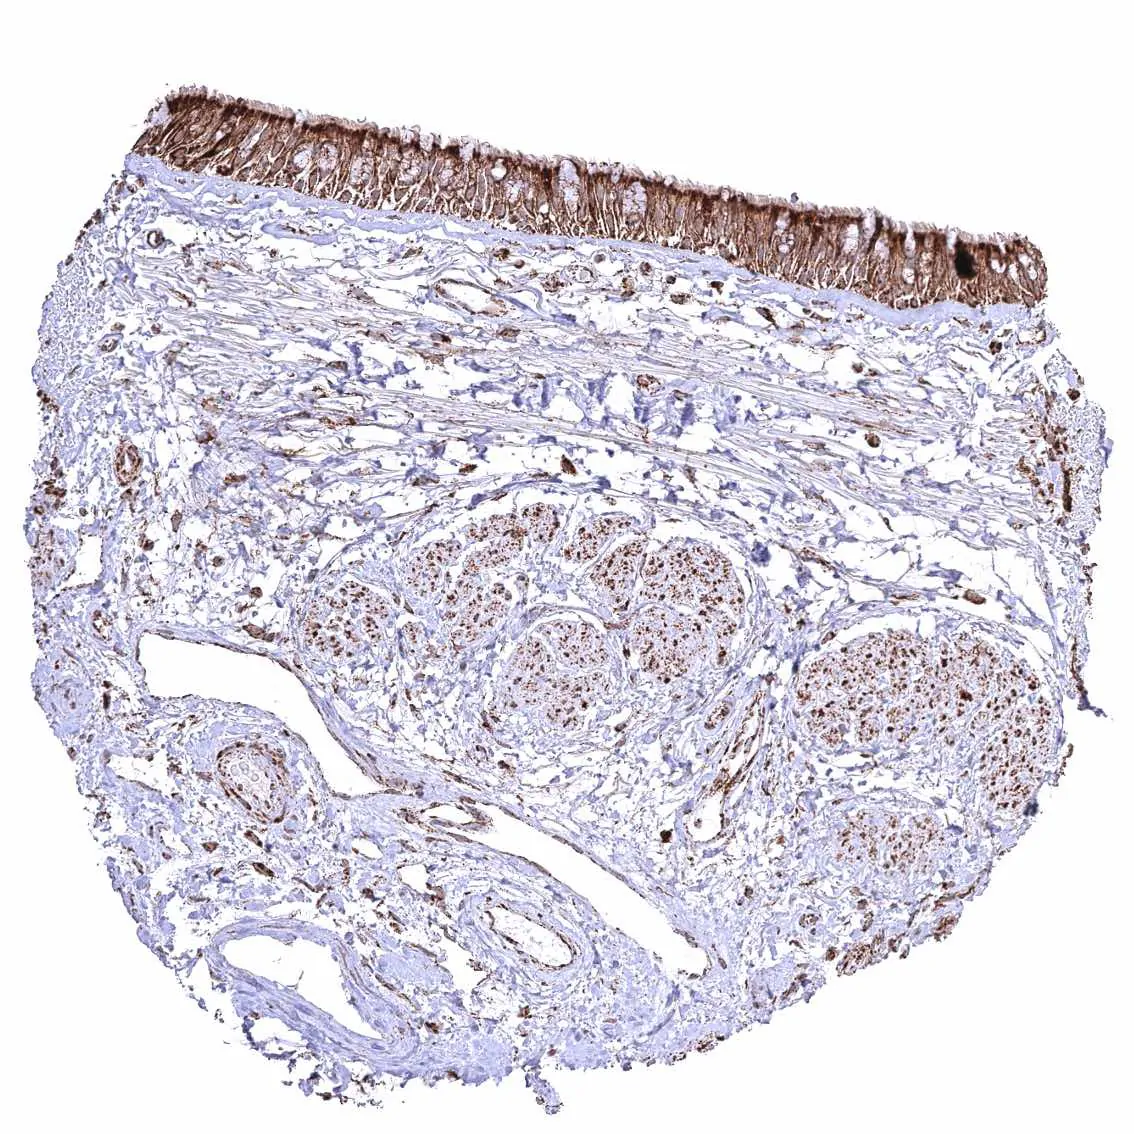

Stomach, corpus – Cytoplasmic ATP5J staining occurs in all cell types. It is most intense in parietal cells and least intense in superficial epithelial cells.